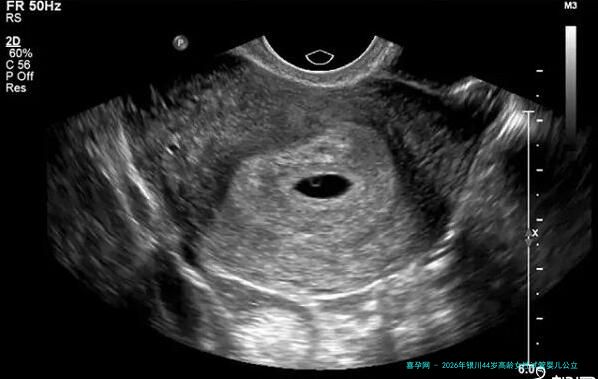

至于四十四岁的高龄女性来说,在银川选择一家靠得住的公立医院做试管婴儿手术,是一个须要谨慎衡量的决断。年龄是影响试管婴儿的关键因素之一,医院的技术力量、医生的经验以及针对高龄女性的个性化方案变得尤其主要。本文将为你提供一个明了的手册,帮助您认知银川关键的公立生殖医学中心,并做出理智的抉择。